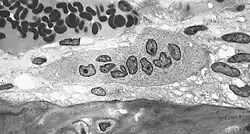

Er vindt in het menselijk lichaam voortdurend ombouw plaats van botweefsel. Cellen met de naam osteoclasten[1] (van het Oudgriekse ὀστέον (osteon) 'bot' en κλαστός (clastos) 'gebroken') breken bot af (osteoclasie), de osteoblasten bouwen bot op. Osteoclasten worden gekenmerkt door een cytoplasma met een homogeen, "schuimig" uiterlijk. Dit uiterlijk is te danken aan een hoge concentratie blaasjes en vacuolen. Deze vacuolen omvatten lysosomen gevuld met zure fosfatase. Dit maakt karakterisering van osteoclasten mogelijk door hun kleuring voor hoge expressie van tartraatresistente zure fosfatase (TRAP) en cathepsine K. Het ruw endoplasmatisch reticulum van osteoclasten is schaars en ze hebben een uitgebreid golgicomplex.[2][3][4] Osteoclasten ontstaan uit de fusie van monocyten, dit leidt tot de vormig van grote, meerkernige cellen. Menselijke osteoclasten hebben doorgaans vier celkernen[5] en hebben een diameter van 150–200 μm. Osteoclasten werden in 1873 ontdekt door Albert von Kölliker.[6]

Osteoclasten worden aangetroffen op die oppervlakken van bot die resorptie ondergaan. Op dergelijke oppervlakken bevinden de osteoclasten zich in ondiepe depressies die resorptie uithollingen worden genoemd (lacunae van Howship). De resorptie uithollingen worden gevormd door de erosieve werking van osteoclasten op het onderliggende bot. De rand van het onderste deel van een osteoclast vertoont vingerachtige uitsteeksels vanwege de aanwezigheid van diepe instulpingen van het celmembraan; deze rand wordt de gerafelde rand genoemd. De gerafelde rand maakt contact met het botoppervlak binnen een resorptie uitholling. De periferie van de gerafelde rand is omgeven door een ringvormige zone van cytoplasma die geen organellen bevat, maar rijk is aan actinefilamenten. Deze zone wordt heldere zone of afdichtingszone genoemd. De actinefilamenten zorgen ervoor dat het celmembraan rondom de afdichtingszone stevig verankerd wordt aan de benige wand van de lacune van Howship. Op deze manier wordt een gesloten subosteoclastisch compartiment gecreëerd tussen de gerafelde rand en het bot dat resorptie ondergaat. De osteoclasten scheiden waterstofionen, collageenase, cathepsine K en hydrolytische enzymen af in dit compartiment. Resorptie van botmatrix door de osteoclasten omvat twee stappen: